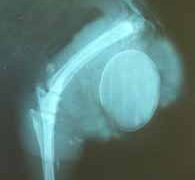

アヒルの病気 アヒルの卵塞症(卵つまり) ~ 雌のアヒルで起こる一般的な産卵関連の問題 卵塞症は、雌のアヒルで起こる一般的な産卵関連の問題です。卵が正常な期間内に卵管を通過できないことと定義されます。卵塞症が起こると、卵管の遠位部に本来あるべきよりも長く卵が存在するために、産卵機能や総排泄腔機能が阻害されることになります。アヒ... 2020.07.19 アヒルの病気